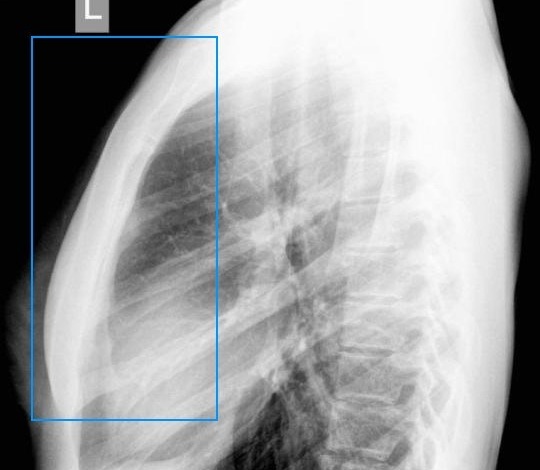

Болезненность в области МО может быть вызвана патологиями дыхательных органов: воспалением легких, бронхитом, туберкулезом, опухолями. Отличить легочные патологии помогает присутствие дополнительных симптомов (кашель, слабость, потливость, повышенная температура).

- Боли в грудной клетке вызывают и заболевания органов дыхательной системы. Это могут быть воспалительные процессы в легком и бронхах, туберкулез, разного вида опухоли и травмы. Сопровождаются кашлем, слабостью, потливостью, повышенной температурой.